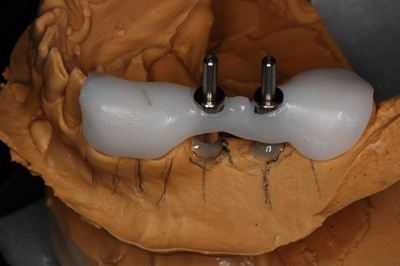

KaVo プロターevo7 咬合器にマウントしました。

スターティングポイントのマーキングのために準備をします。

近心側は角度も決めていますが、

遠心側はスターティングポイントのマークまでの役割です。

便宜的に平行にしてサージカルステントが着脱できるようにしています。